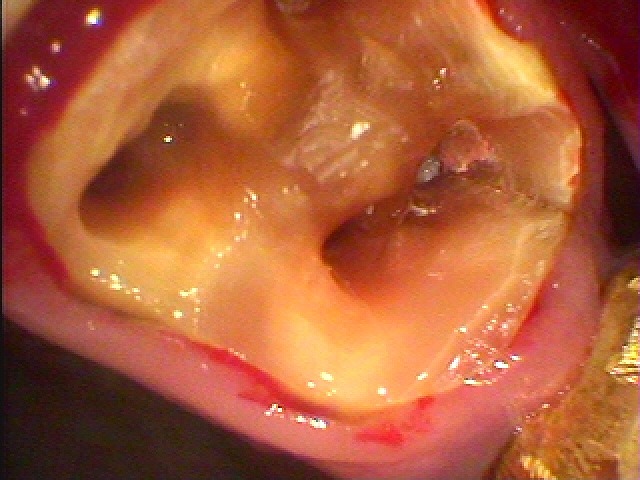

左下6番、破折によりインプラント即時埋入|お知らせ |広島市安佐南区の歯科医院 左下6番、破折によりインプラント即時埋入 トップ お知らせ・ブログ お知らせ 左下6番、破折によりインプラント即時埋入 左下6番、破折によりインプラント即時埋入 近心根に器具の破折が見て取れます 症状もありかぶせを外して根の治療をしていきます 被せをを外していきました これより根の治療をしていきます 土台を外していきます この歯は割れていました 抜歯をさせていただきました 補填材を入れ、インプラント埋入終了 CTデータになります 術前と述語になります Web診療予約 初めての方へ 選ばれ続ける理由 院内設備について 歯が痛いしみる一般歯科 歯がぐらぐらする歯周病 健康な歯を保ちたい予防歯科 子供の虫歯予防をしたい小児歯科 銀歯をセラミックに審美歯科 白い歯を目指しませんか?ホワイトニング 矯正専門医がいるので安心矯正歯科 抜けた歯を補いたいインプラント・入れ歯 医院案内 スタッフ紹介 メリィハウス歯科クリニックオフィシャルホームページ ラベンダー歯科クリニックオフィシャルホームページ お知らせ・ブログ ホーム 診療科目 一般歯科 歯周病治療 予防治療 小児歯科 審美治療 ホワイトニング 矯正歯科 入れ歯・インプラント マウスピース矯正 初めての方へ 院長・スタッフ 設備紹介 医院案内・アクセス メニューを閉じる